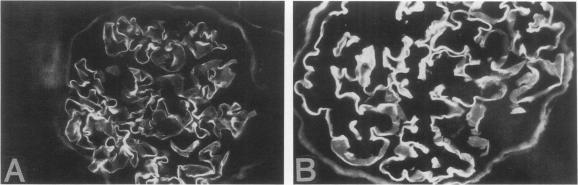

Diabetic nephropathy is characterized by progressive expansion of mesangial matrix and thickening of the glomerular basement membrane (GBM). Kidney tissues from 13 patients with insulin-dependent diabetes mellitus were studied by immunohistochemical techniques for the distribution of three recently described collagen peptides (M28+, M28 [Good-pasture antigen], and Alport antigen) and various components of classical type IV collagen [alpha 1(IV) noncollagenous (NC) globular domain, alpha 2(IV) NC, 7S, triple helix]. Recently M28 and M28+ were designated as NC monomers of alpha 3(IV) and alpha 4(IV) based on limited amino acid sequencing. During the course of the disease, the distribution of the M28 chains and the Alport peptide segregated completely from that of classical type IV collagen. In diabetic kidneys, antibodies to the M28 and Alport peptides reacted intensely with the thickened GBM but not with the mesangium. In contrast, the reactivity of antibodies to various components of classical type IV collagen was prominent within the expanded mesangial matrix with significant decrease in reactivity in the peripheral capillary wall. In hyalinized glomeruli, components of classical type IV collagen virtually disappeared, whereas the M28 and Alport peptides persisted in the collapsed GBM. These studies support the view that expansion of the mesangial matrix and thickening of the GBM involve separate and distinct collagen components. The differential expression of the M28 and Alport peptides compared with that of classical type IV collagen may be a consequence of differing sites of synthesis (classical type IV collagen from endothelial/mesangial cells and M28 and Alport chains from visceral epithelial cells), independent control mechanisms, and/or differences in degradation.

糖尿病肾病的特征是系膜基质进行性扩张和肾小球基底膜(GBM)增厚。采用免疫组织化学技术,对13例胰岛素依赖型糖尿病患者的肾组织进行研究,观察三种最近描述的胶原肽(M28 +、M28[古德帕斯丘抗原]和奥尔波特抗原)以及经典IV型胶原的各种成分[α1(IV)非胶原(NC)球状结构域、α2(IV) NC、7S、三螺旋]的分布情况。最近,基于有限的氨基酸测序,M28和M28 +被指定为α3(IV)和α4(IV)的NC单体。在疾病过程中,M28链和奥尔波特肽的分布与经典IV型胶原的分布完全分离。在糖尿病肾中,针对M28和奥尔波特肽的抗体与增厚的GBM强烈反应,但与系膜无反应。相反,针对经典IV型胶原各种成分的抗体反应在扩张的系膜基质中很突出,而在外周毛细血管壁中的反应性显著降低。在玻璃样变的肾小球中,经典IV型胶原成分几乎消失,而M28和奥尔波特肽仍存在于塌陷的GBM中。这些研究支持这样一种观点,即系膜基质的扩张和GBM的增厚涉及不同的胶原成分。与经典IV型胶原相比,M28和奥尔波特肽的差异表达可能是由于合成部位不同(经典IV型胶原由内皮/系膜细胞合成,M28和奥尔波特链由脏层上皮细胞合成)、独立的控制机制和/或降解差异所致。